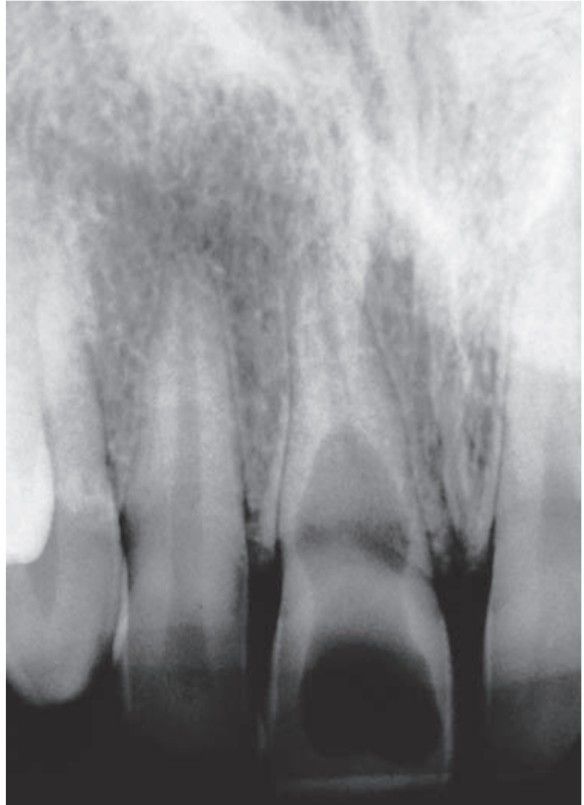

Internal resorption

Resorption of the dentin of the pulpal walls may be seen as part of an inflammatory response to pulpal injury, or it may be seen in cases in which no apparent trigger can be identified